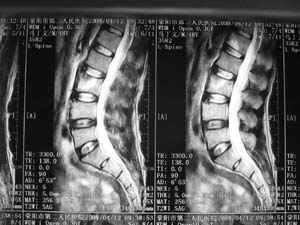

标题: MRI2131:男,腰痛三月向右下肢放射一月余 [打印本页]

标题: MRI2131:男,腰痛三月向右下肢放射一月余

骨质轻微破坏,硬化明显,椎管未见异常,考虑良性骨瘤的可能性大,

椎体增生 硬化 囊变。考虑:退变!

支持考虑退变,许莫结节形成

椎体前缘骨质增生硬化、囊变。椎旁软组织未见确切异常。考虑椎体前缘软骨结节。

1)l3椎体前上缘许莫氏结节形成。2)腰椎退行性改变。

l3椎体前上缘许氏结节。

退变,许莫氏结节.腰1椎体血管瘤.

l2大部分椎体信号增高-----脂肪变性,转移待排。l3 椎体t2 低信号考虑硬化增生。